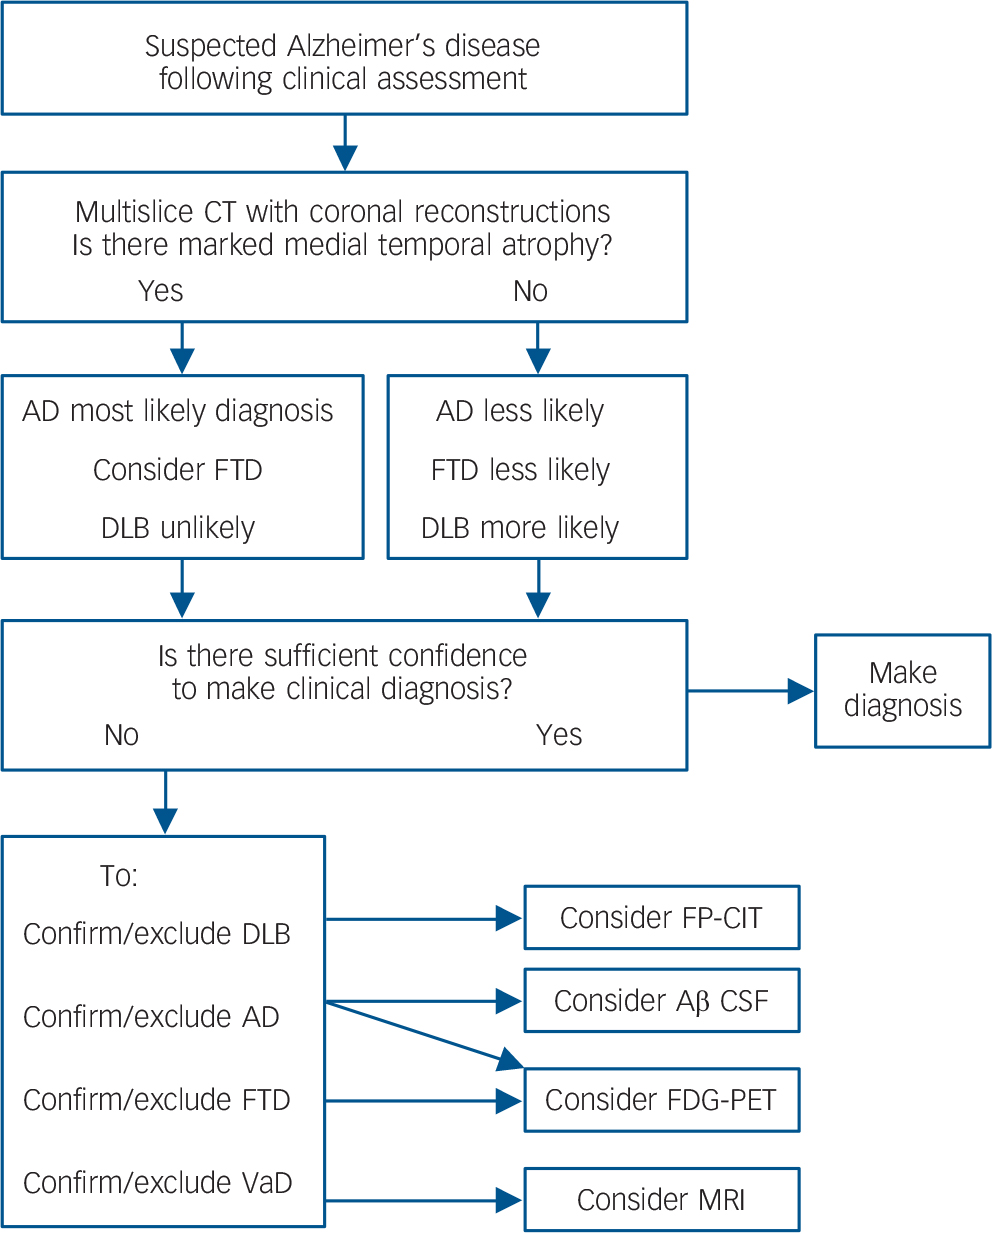

95% confidence interval in brackets. PET ROI is the MTL/occipital uptake ratio. The CT & PET visual rating figures are obtained by following the diagnostic flowchart in Fig. 3, i.e. an Alzheimer's disease diagnosis is given via either MTLA on CT, or Alzheimer's disease positive FDG-PET scan following normal MTL on CT. CT, computed tomography; DLB, dementia with Lewy bodies; MTL, medial temporal lobe; MTLA, medial temporal lobe atrophy; PET, positron emission tomography; ROI, region of interest.

Many countries, including the UK, have initiatives aimed at raising the profile of dementia and increasing the numbers diagnosed, with some research estimating that currently less than half the people with dementia receive a formal diagnosis. Reference Connolly, Gaehl, Martin, Morris and Purandare39 There will also be a substantial increase in the numbers of patients with dementia over the next 40 years, due to increases in lifespan. 40 Neuroimaging services will be an important part of providing diagnoses to these increasing numbers. However, FDG-PET remains a relatively expensive option and involves a rather lengthy procedure for the patient compared to a CT scan. Therefore, to maximise health care resources, and minimise unnecessary investigations for people with dementia, FDG-PET will have to be used only as part of an evidence based diagnostic pathway. Based on our results, a suggested algorithm for considering neuroimaging, dependent on both the CT results and the clinical question, is presented in Fig. 3. Future work should seek to incorporate other imaging biomarkers into this algorithm, for example, amyloid-PET.

Fig. 3 Evidence-based imaging algorithm for FDG-PET use.

DLB, dementia with Lewy bodies; FTD, fronto-temporal dementia; FP-CIT, single-photon emission computed tomography with FPCIT (dopamine transporter) ligand; CT, computed tomography; FDG-PET, fluorodeoxyglucose positron emission tomography; VaD, vascular dementia; Aβ, amyloid-beta; CSF, cerebrospinal fluid.